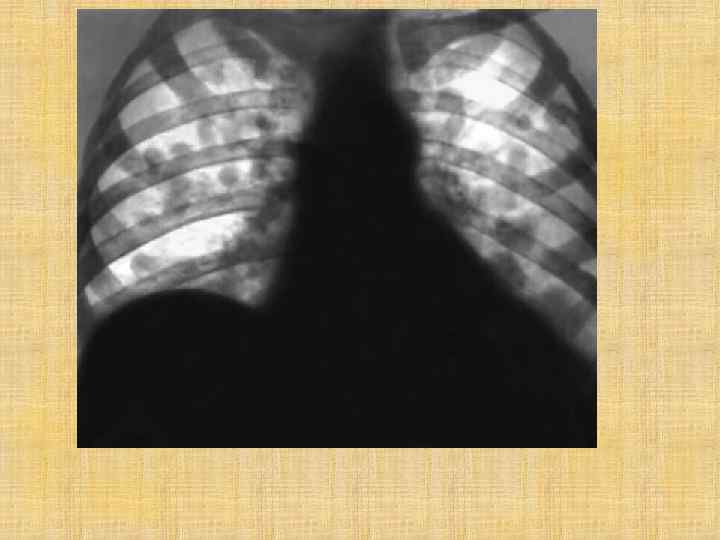

Муковисцидоз